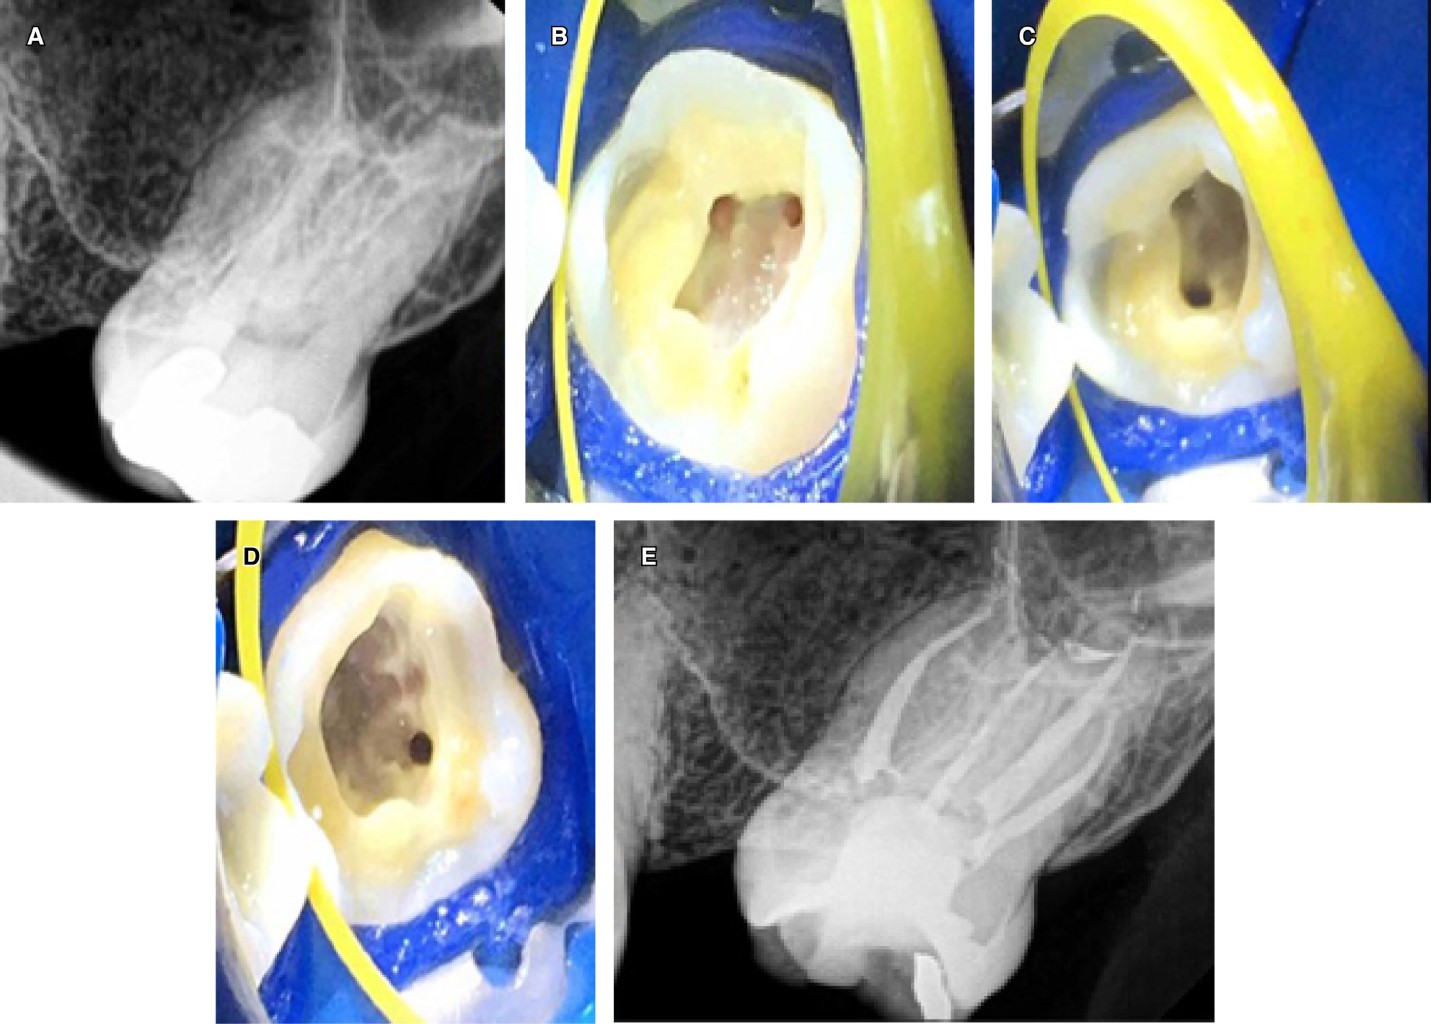

Se presentó una mujer de 28 años de edad con antecedentes médicos no contributivos con dolor a los cambios térmicos en el segundo molar maxilar derecho. Clínicamente, se observó la presencia de una amalgama fracturada y caries profunda. Desde el punto de vista radiográfico, el ancho del espacio del ligamento periodontal (PLS) era normal y no había patología periapical. Hubo una respuesta prolongada al frío y una prueba de percusión vertical positiva, con ausencia de bolsas periodontales. El diagnóstico pulpar fue pulpitis irreversible sintomática y el diagnóstico periapical fue de periodontitis apical sintomática. Después de la técnica de anestesia local con lidocaína con epinefrina al 1:80,000, el tratamiento se realizó con aislamiento absoluto con dique de hule y aumento con lupas (3.5x). La amalgama se retiró con fresas de diamante y luego la cavidad de acceso se diseñó con fresas de carburo y puntas ultrasónicas Star X (Dentsply Sirona). La cavidad de acceso tenía un diseño cuadrangular y se ubicaron cuatro conductos radiculares. Cada uno de los cuatro conductos se negoció una lima k10/02 (Dentsply Maillefer, Ballaigues, Suiza) precurvada. Se tomó la longitud de trabajo con un localizador de ápices (Root ZX, J. Morita, Tokio, Japón) y se confirmó con una radiografía dentoalveolar digital. Para la instrumentación de los conductos radiculares se usó el sistema Mtwo® (VDW, Alemania). Los conductos vestibulares fueron instrumentados a 35/04 y los dos conductos palatinos a 40/04. El protocolo de irrigación y la técnica de obturación fueron los mismos que en el caso anterior (Figura 2A-E).

La identificación radiográfica preoperatoria de una raíz adicional tiene algunas dificultades. Estas dificultades pueden incluir la superposición de estructuras anatómicas como se observa en las radiografías preoperatorias de los dos casos presentados.13 Si el contorno de las raíces no se observa claramente en una radiografía, se deben tomar más radiografías con diferentes angulaciones para identificar o descartar la presencia de variaciones anatómicas (Figuras 1A y 2B). Algunas de las técnicas de angulación para tomar radiografías han sido revisadas previamente por Fava y colaboradores.13 Las radiografías siempre tendrán ciertas limitaciones, independientemente de las técnicas de angulación utilizadas, la imagen radiográfica es una sombra y es una representación bidimensional de un objeto tridimensional.14 A pesar de estos desafíos, las radiografías dentoalveolares preoperatorias de buena calidad podrían ser muy útiles en la identificación de características radiográficas (como la lámina dura y el ligamento periodontal) que pueden interpretarse de manera más consistente que otras15 y que nos puede proporcionar información para una mejor determinación del número y la forma de las raíces en los molares superiores.16 Cuando las raíces de los dientes parecen ser más largas que la longitud promedio (20 mm) o la longitud máxima (24 mm), esto puede ser una indicación de una raíz adicional (Figura 1A-C). Por ejemplo, algunos casos reportan segundos molares maxilares con dos raíces palatinas con una longitud de la raíz palatina igual o superior a 26 mm.17 Por lo general, utilizando la técnica de ángulo de bisección estándar, la raíz palatina se puede ver detrás y en el medio de la raíz distobucal y mesiobucal en una radiografía. Si la raíz palatina no se pudiera identificar en la posición mencionada anteriormente (Figuras 1A y 2A), esto sería una indicación de una variación anatómica como la presencia de una raíz palatina adicional. Para una correcta identificación de la raíz palatina en esta situación es aconsejable tomar más radiografías que modifiquen la angulación vertical u horizontal para obtener una imagen no superpuesta de las estructuras de interés (Figuras 1C y 2C). La radiografía de la longitud de trabajo también puede confirmar la presencia de dos raíces palatinas si el instrumento parece estar alejado del centro de la raíz.18,19